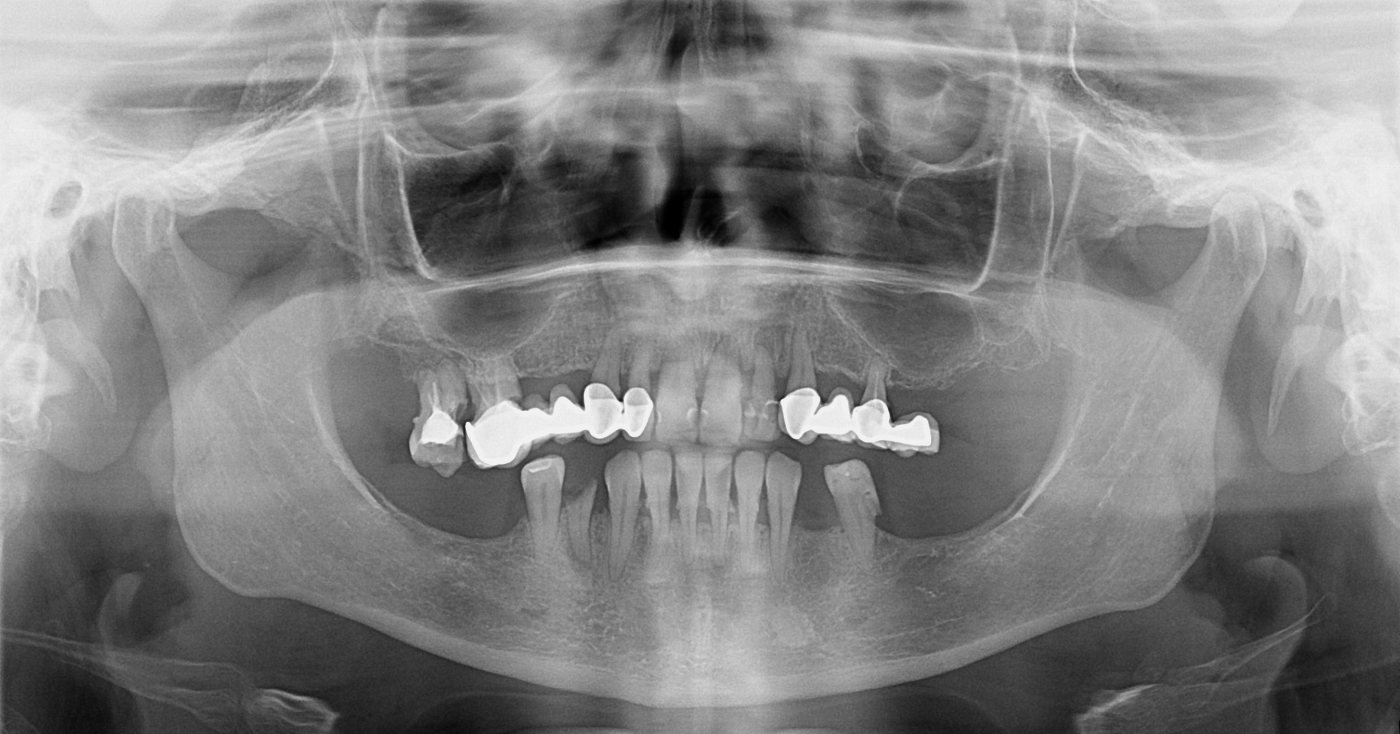

Ortopan snimka: trajni All-on-4 rad na titanskoj prečki s krunicama od cirkon-oksidne keramike